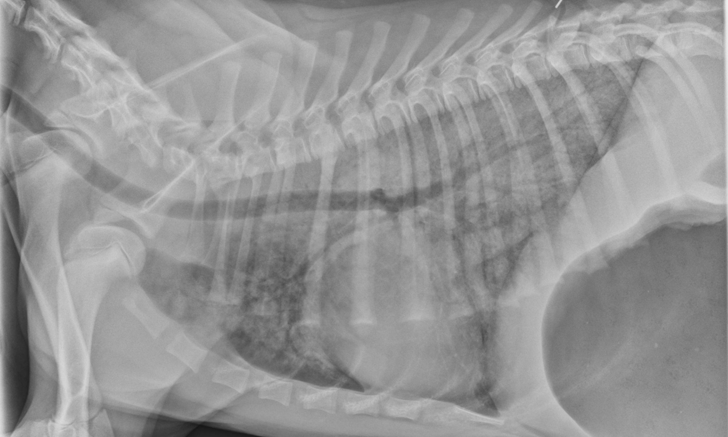

Thoracic radiographs can appear normal initially, but changes to the pulmonary parenchyma may become more apparent within 24 to 72 hours as respiratory injury progresses. Evidence of patchy pulmonary edema with bronchial, interstitial, or alveolar patterns may be observed [Figures 1 and 2].6,13,16,19 Right middle lung lobe consolidation and pleural effusion in cats have been reported.6,13,16 An alveolar pattern may be seen on serial radiographs in patients that develop secondary bacterial pneumonia.6

VD thoracic x-ray of dog showing opacity of lung parenchyma concentrated in caudal fields and overlapping cardiac silhouette.

FIGURE 2

A severe, patchy interstitial-to-alveolar pattern, more severe in the left hemithorax and caudodorsal lung fields, in a dog with smoke inhalation injury after a house fire